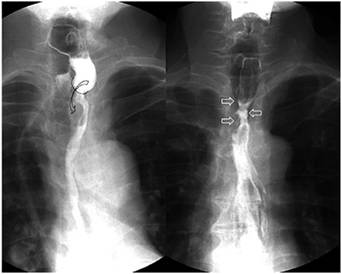

La disfagia cardiovascular hace referencia a múltiples enfermedades de naturaleza cardiovascular que causan compresión esofágica y disfagia secundaria; estas se pueden dividir en congénitas (doble arco aórtico, arco aórtico derecho, arco aórtico cervical, divertículo de Kommerell, arteria subclavia aberrante, arteria pulmonar en cincha, ligamento arterioso), adquiridas (disección aórtica, escoliosis, crecimiento de la aurícula izquierda) o iatrogénicas (fistula aortoesofágica, disfagia posoperatoria) 21,22.

El crecimiento de la aurícula izquierda secundario a enfermedades congénitas o adquiridas y asociado con estenosis mitral puede causar compresión esofágica con disfagia secundaria; esta constituye un diagnóstico diferencial en el estudio de la disfagia. Cuando el crecimiento de la aurícula es secundario a una valvulopatía mitral reumática y a parálisis del nervio laríngeo recurrente izquierdo, se conoce como síndrome de Ortner o disfagia cardiovocal21-23 (Figura 8).